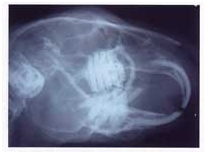

in the gingiva). This feature is clearly visible on the X-ray of Figure 2

Figure

2 : X-ray of a rabbit skull